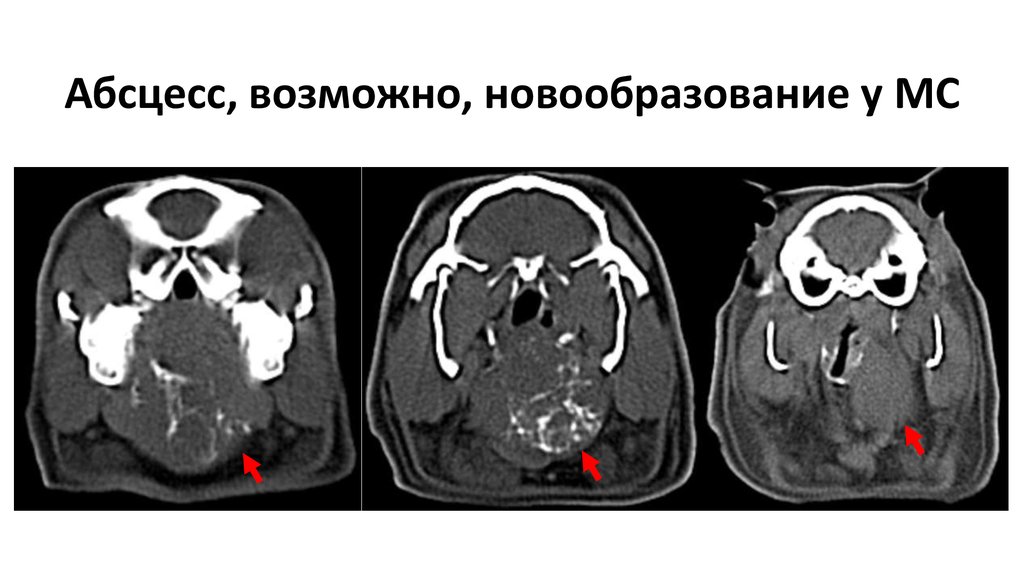

44. Абсцесс, возможно, новообразование у МС